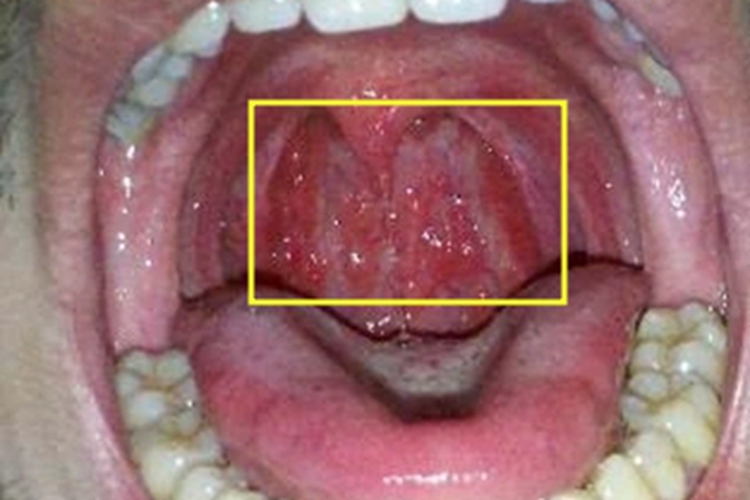

淋菌性咽炎的黏膜损害,可表现为局部出现疙瘩,呈水疱样损害,散在分布,表面透明、发红,大小不一,为微微凸起的圆形,周围黏膜轻微红肿,患者自觉有咽干、咽痛和吞咽痛等表现。